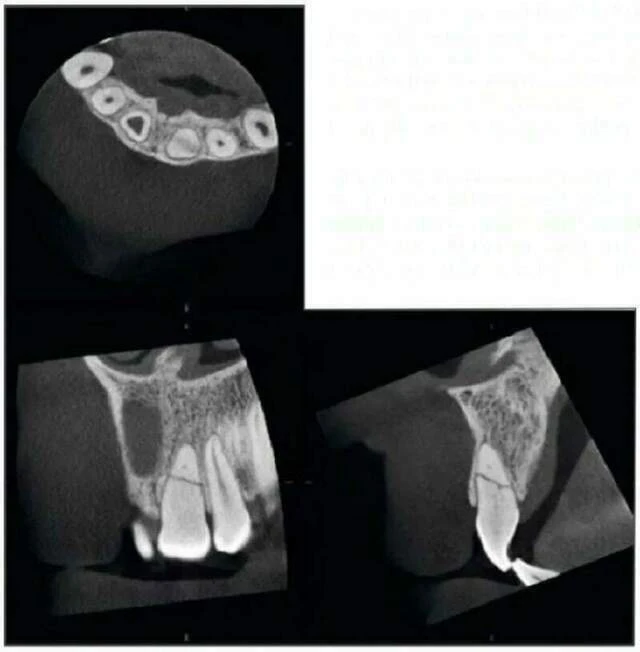

Chụp kiểm tra bằng Accuitomo vùng răng hàm trên phía trước cho thấy răng cửa giữa hàm trên bên phải có một ống tuỷ rất rộng. Điều này có thể thấy ở răng bị chết tuỷ từ khi tuổi còn nhỏ. Tại chóp răng này, thấy có một nang lớn. Bờ của nó không rõ và xương xung quanh đặc hơn bình thường. Tổn thương vì vậy có hình ảnh của một nang nhiễm trùng quanh chóp. Kiểm tra còn cho thấy một đường nứt ở phần chóp của răng cửa giữa bên phải.

Ở răng cửa giữa bên trái, thấy một đường gãy hầu như nằm ngang qua chân răng. Mảnh gãy phía chóp và phía thân răng, tuỷ răng hầu như bị hoại tử sạch.